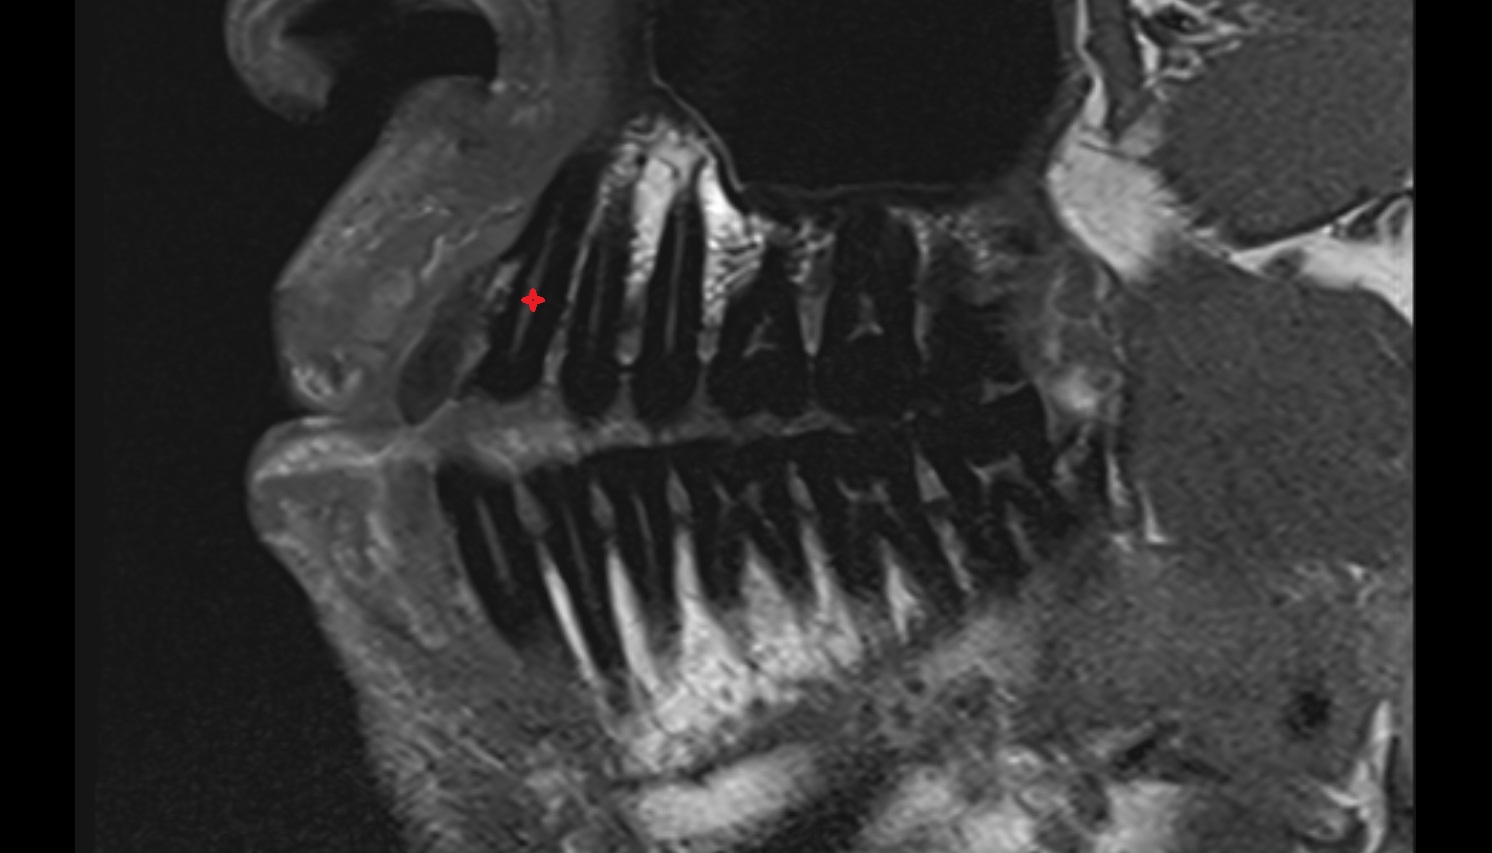

- Inferior canine tooth

- Inferior cornu of thyroid cartilage

- Inferior first premolar tooth

- Inferior second molar tooth

- Inferior second premolar tooth

- Inferior third molar tooth

- Lateral inferior incisor tooth

- Lateral superior incisor tooth

- superior canine tooth

- Superior first molar tooth

- Superior first premolar tooth

- Superior second molar tooth

- Superior second premolar tooth

- Superior third molar tooth

- Root of lower molar tooth

- Lower molar apical foramen

- Upper premolar apical foramen

- Root of upper molar tooth

- Root canal of upper molar tooth

- Dental pulp of upper molar tooth

- Dental pulp of upper premolar tooth

- Enamel of canines tooth

- Enamel of lower molar tooth

- Root canal of upper premolar tooth

- Root canal of upper canines tooth

- Enamel of upper molar tooth

- Enamel of upper incisor tooth

- Enamel of lower canines tooth

- Enamel of lower incisor tooth

- Enamel of lower premolar tooth

- Dental pulp of lower molar tooth

- Root canal of lower premolar tooth